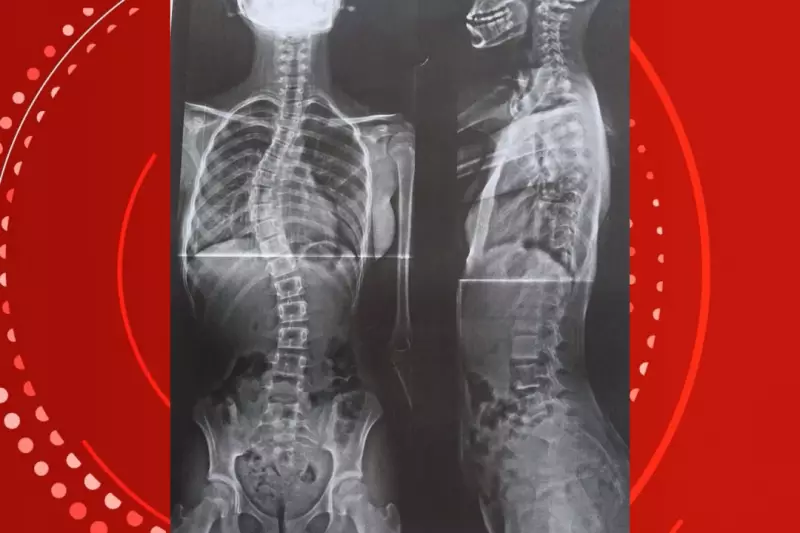

Sua filha, uma garotinha de apenas 11 anos, convive com uma escoliose severa - aquela condição onde a coluna decide formar um "S" em vez de seguir reta. E não é qualquer curvatura, não. Estamos falando de algo que já passa dos 40 graus, um número que assustaria qualquer especialista.

O que mais corta o coração nessa história toda é o timing. A menina está justamente na fase de crescimento - entre 10 e 12 anos - que é quando a escoliose mais progride. É como tentar consertar um barco enquanto ele ainda está navegando em águas turbulentas.

Sem o colete adequado, a situação pode evoluir para algo ainda mais grave. Estamos falando de possíveis complicações respiratórias, dores crônicas que ninguém merece viver, especialmente uma criança. E aí a solução pode acabar sendo uma cirurgia de alto risco - exatamente o que todos querem evitar.